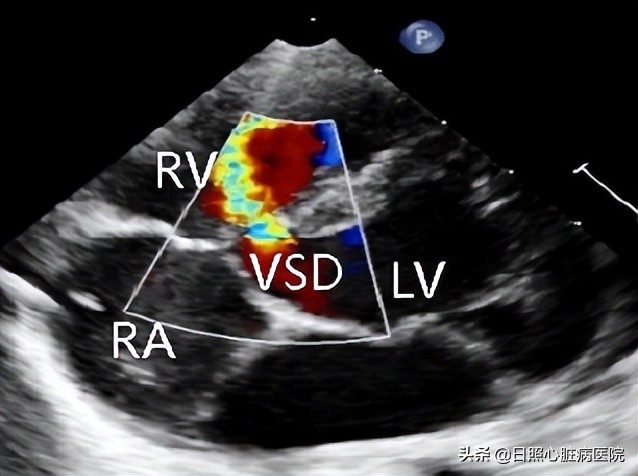

若室间隔存在异常开口,“墙上”破了个洞,造成左右心室血流异常流通,就是室间隔缺损。

室间隔缺损是最常见的先天性心脏病之一,约占成年人先天性心血管疾病的15%-20%。

当出现室间隔缺损相关的临床表现时需要做心电图、胸部x线片检查、超声心动图检查帮助诊断。其中超声心动图是首选的检查手段,它可以精确的诊断出缺损口大小、分流及部位。